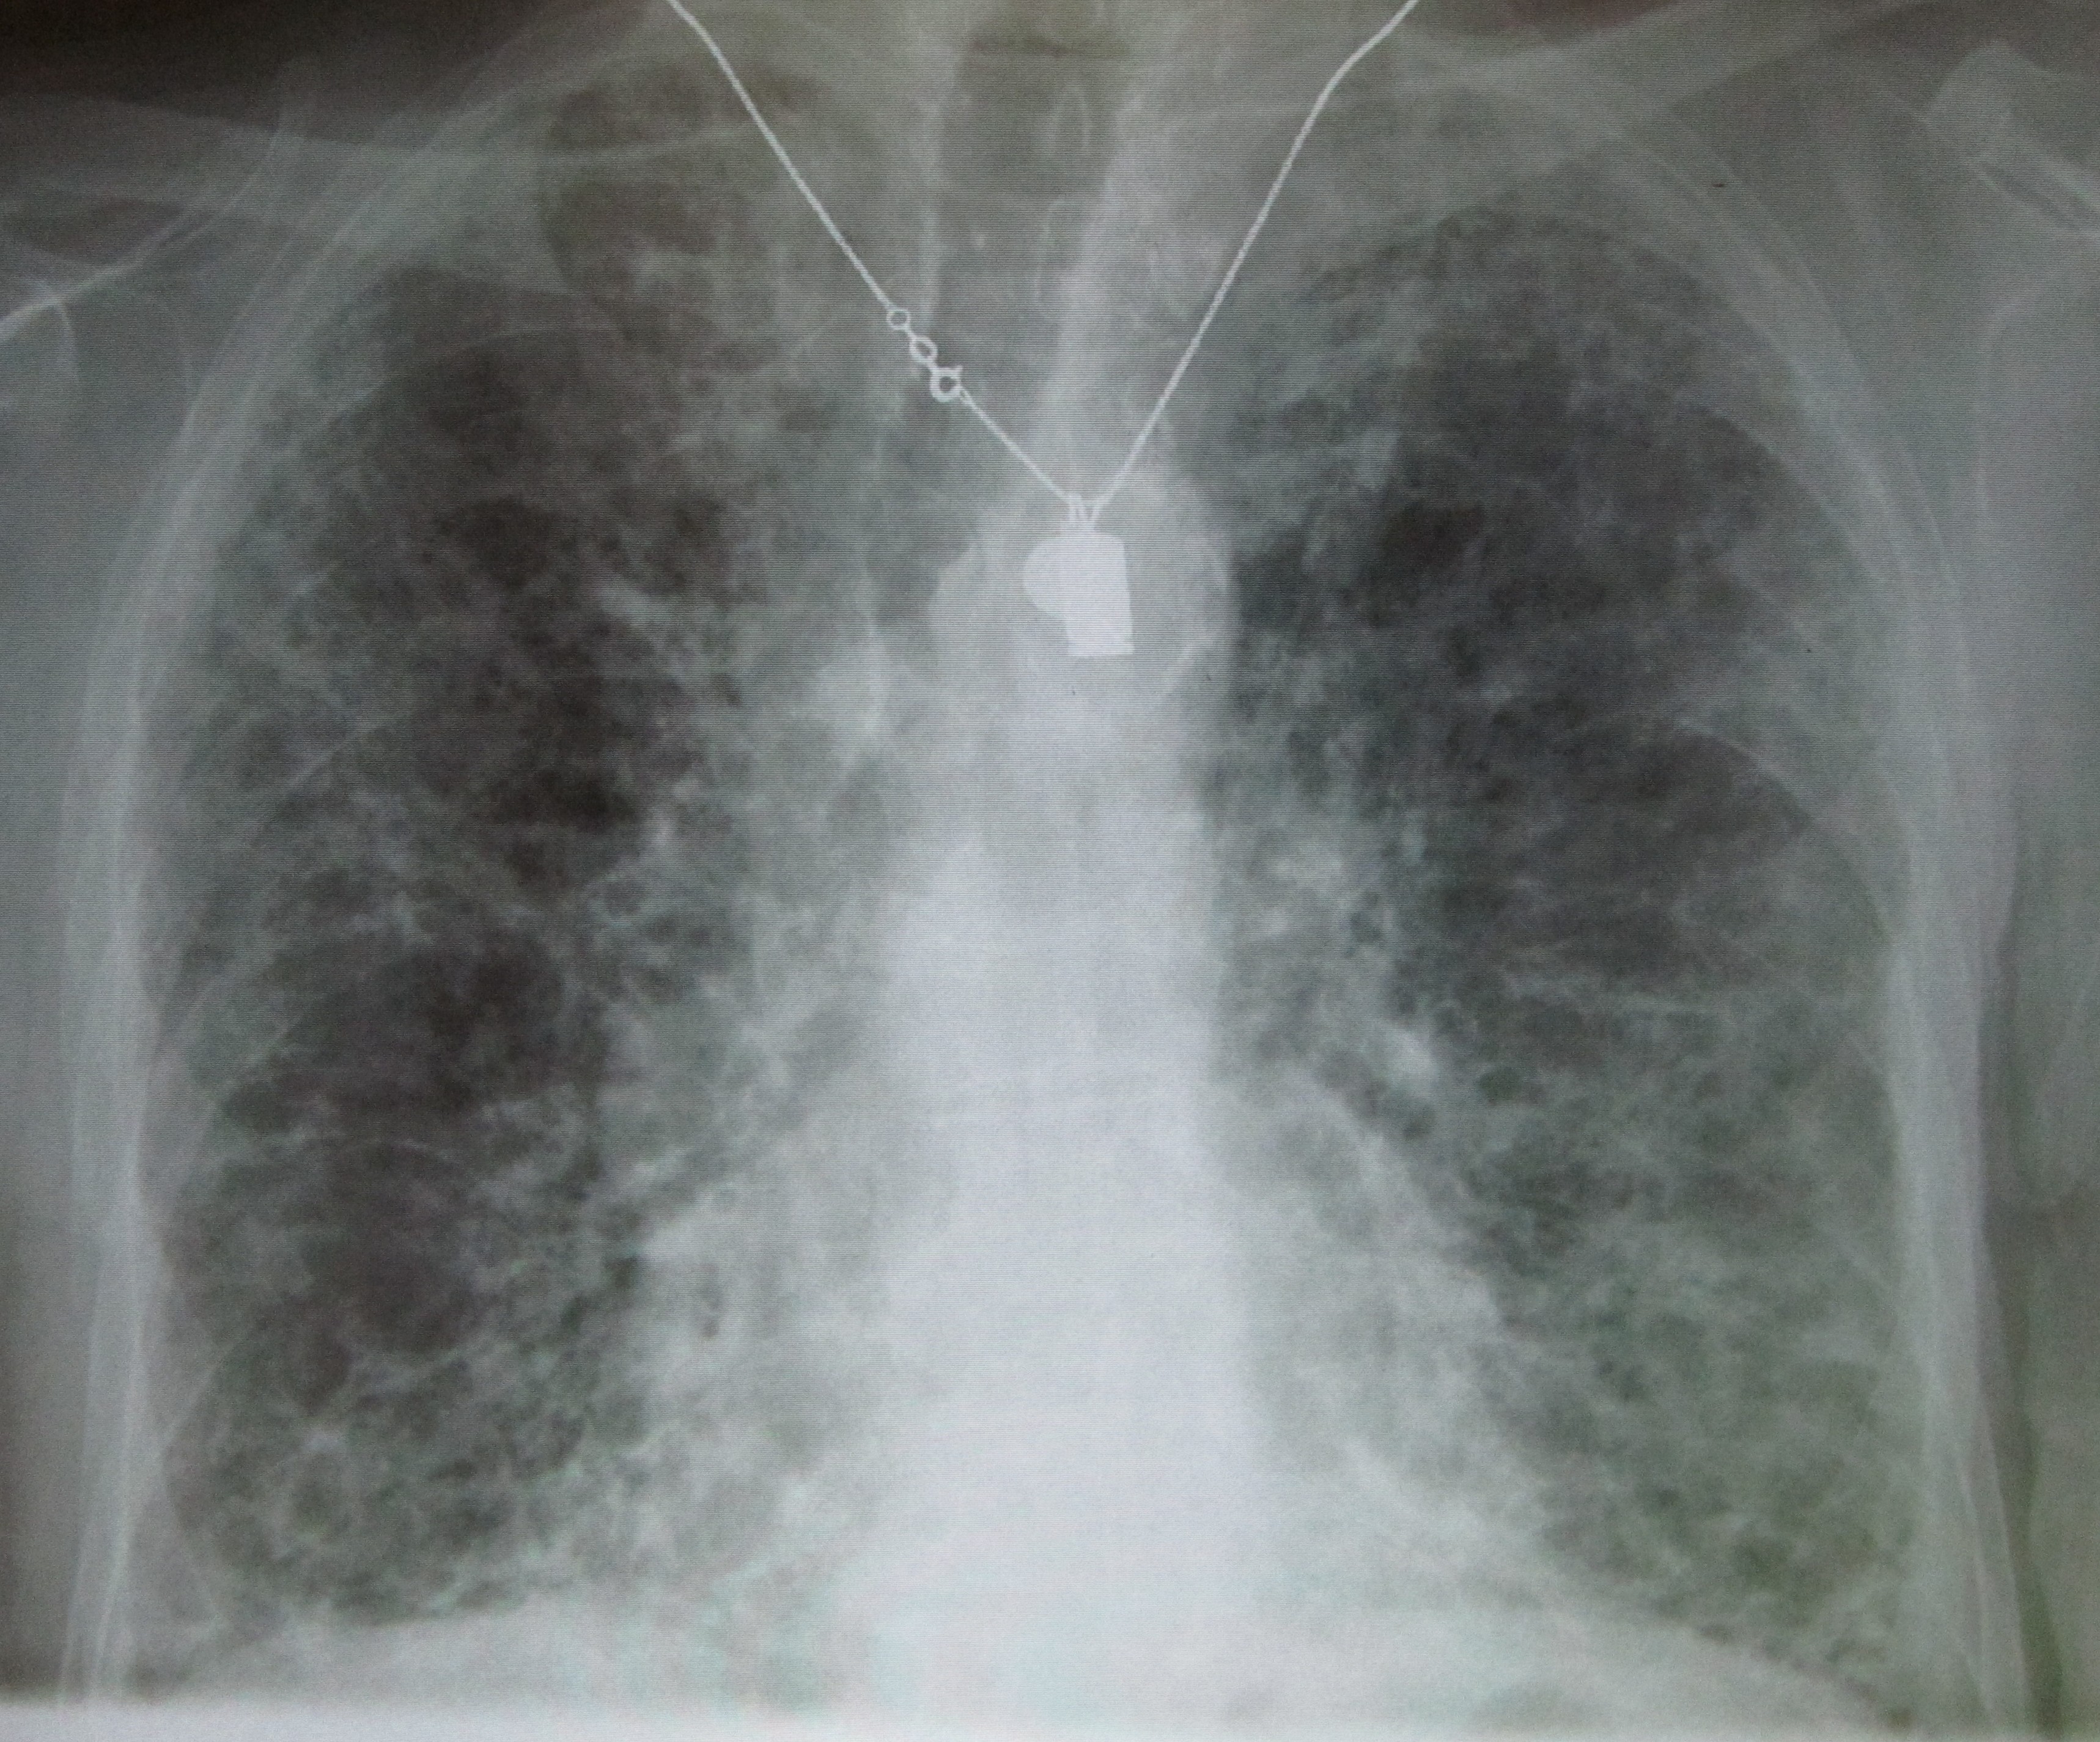

흉부 엑스레이는 ILD에 대해 63%의 민감도와 93%의 특이도를 보인다.[6] 컴퓨터 단층 촬영의 발전으로 인해 흉부 CT 스캔은 ILD의 선호되는 진단 검사로 폐 생검을 대체했다. 흉부 CT 스캔은 ILD에 대해 91%의 민감도와 71%의 특이도를 보인다.[6] 고소득 국가에서는 ILD 환자의 10% 미만이 진단 평가의 일환으로 폐 생검을 받는다.[14]

흉부 방사선 사진은 일반적으로 간질성 폐 질환을 감지하기 위한 첫 번째 검사이지만, 특히 질병 과정의 초기에는 흉부 방사선 사진이 최대 10%의 환자에서 정상으로 나타날 수 있다.[17][18]

진단상 중요한 것은 영상 검사이다. 단순 X선 촬영 및 흉부 CT에서는 '''유리 갈림 음영'''이 특징적이다. 이는 비교적 균일하게 농도가 올라간, 흐릿한 폐 음영이다. 진행되면 섬유화를 반영하여 벌집 모양을 띠게 된다.